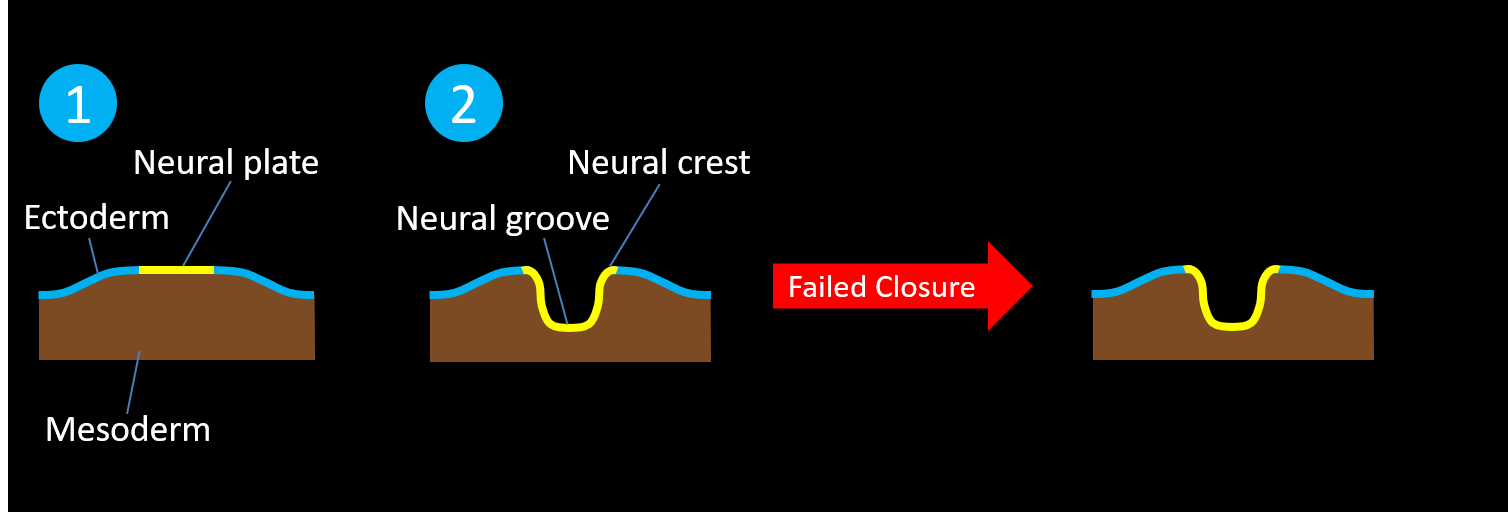

- Failed closure and failed separation of the neural tube from the ectoderm results in open neural tube defects (i.e. defects with no skin covering), including:

- Myelomeningocele – the meningeal lining and the neural placode extend beyond the skin surface

- Myelocele – the neural placode remains flush with skin surface

- Failed closure and failed separation of the neural tube from the ectoderm results in open neural tube defects (i.e. defects with no skin covering), including:

-

-

-